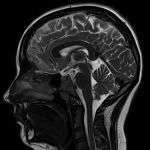

Что показывает МРТ головного мозга

Магнитно-резонансная томография предоставляет возможность четко просмотреть любое нарушение в тканевой структуре. Это единственный способ узнать происходит ли деформация в сосудах, а также различного типа отклонения в кровоснабжении. Благодаря этому, можно диагностировать развитие раннего инсульта, а затем успешно вывести человека из состояния кризиса.

МРТ высокоэффективно при подозрении на онкологические заболевания, травмы мозга, гематомы. Другими словами, опираясь на полученные снимки, врачу удается узнать наличие болезни, ее расположение, структуру и форму. Далее он выписывает подробное заключение, показание и передает в руки вашему лечащему врачу.